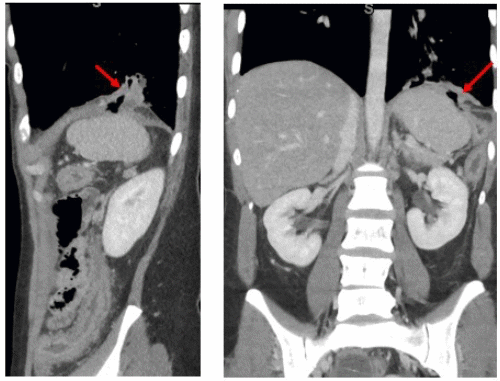

After she was admitted to the hospital and started on Solu-Medrol, her abdominal pain and diarrhea improved, but she continued to cough up bilious secretions. Her sputum gram stain contained 2+ species of Gram-negative rods. She underwent colonoscopy prep, which incited increasing respiratory symptoms, including coughing up copious amounts of secretions. This, along with sputum Gram stain, increased the suspicion for colobronchial fistula and prompted further workup. A barium enema was obtained, which confirmed the presence of a colobronchial fistula (Figure 2.)

Figure 2. Barium Enema Confirming Presence of Colobronchial Fistula. Published with Permission